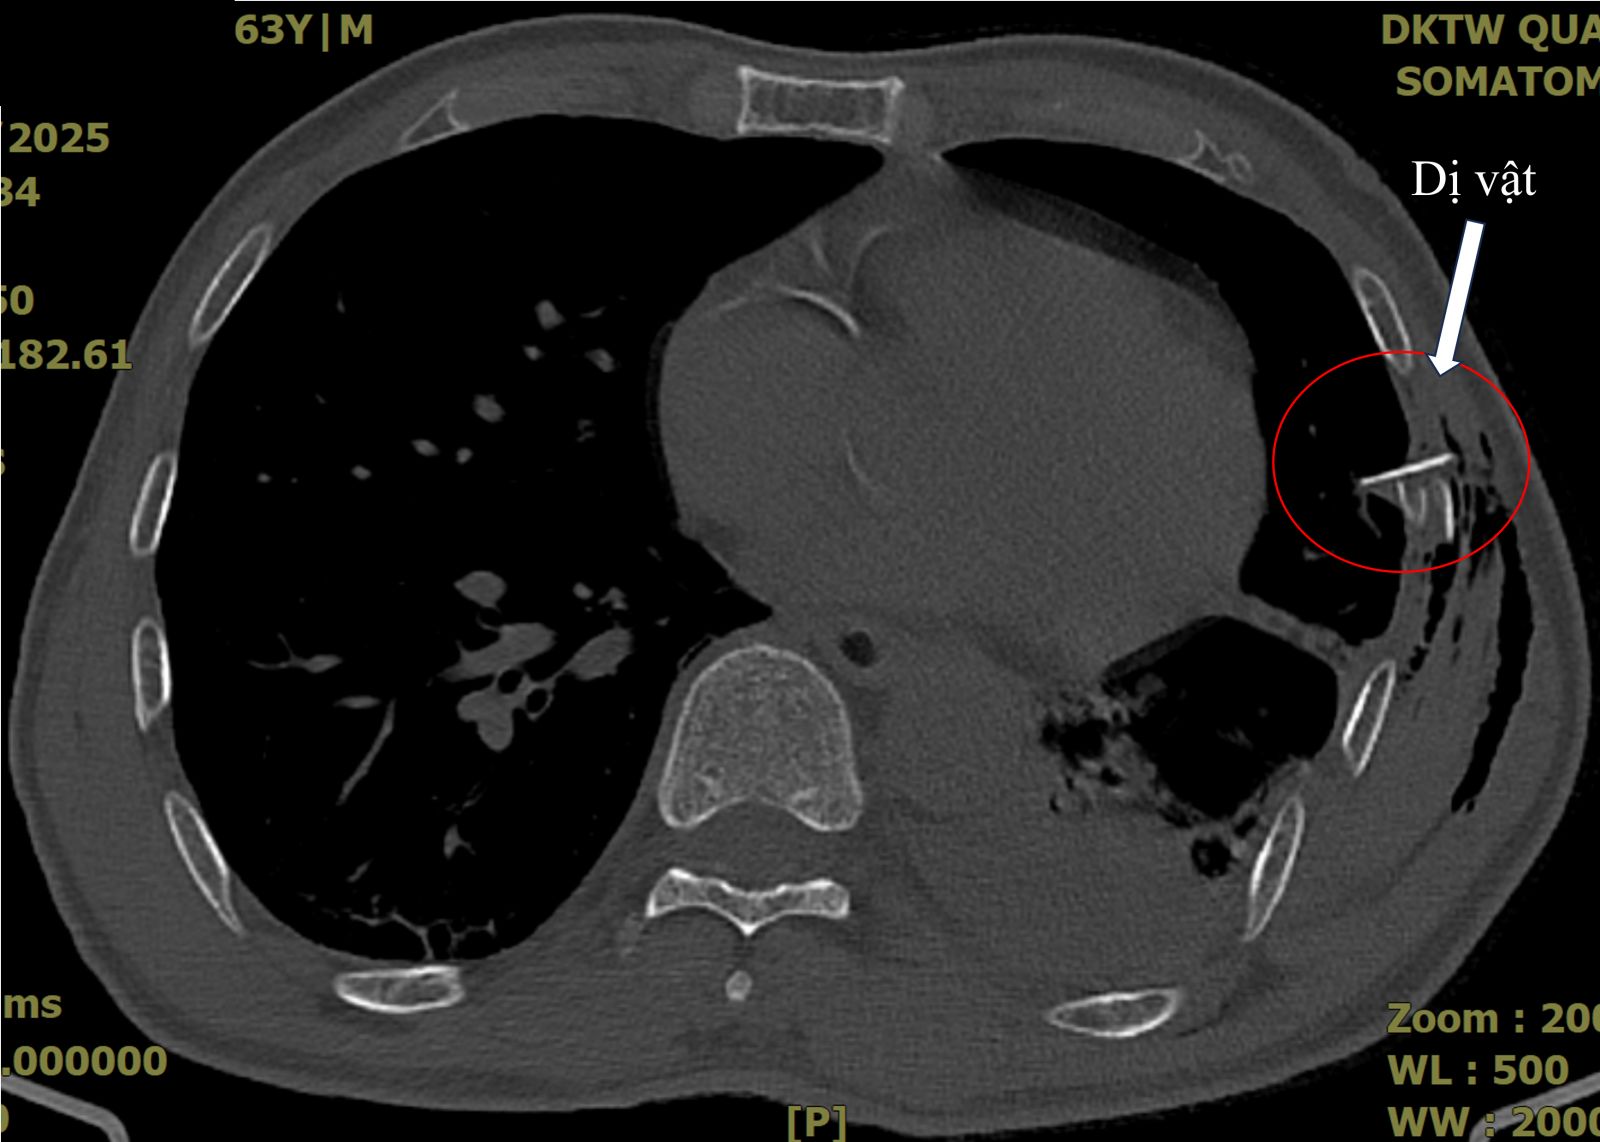

Hình ảnh chụp cắt lớp ngực ghi nhận bệnh nhân bị tràn khí, tràn máu màng phổi với một hình ảnh mảnh xương sườn đâm vào nhu mô phổi.

Sau đó, bệnh nhân có cơn đau ngực tăng dần, đau không dám thở, trong tình trạng suy hô hấp, hình ảnh X-quang phổi chưa ghi nhận bất thường khác ngoài gãy các xương sườn VI, VII, VII. Bệnh nhân được chụp cắt lớp ngực và ghi nhận tràn khí, tràn máu màng phổi với một hình ảnh mảnh xương sườn đâm vào nhu mô phổi.